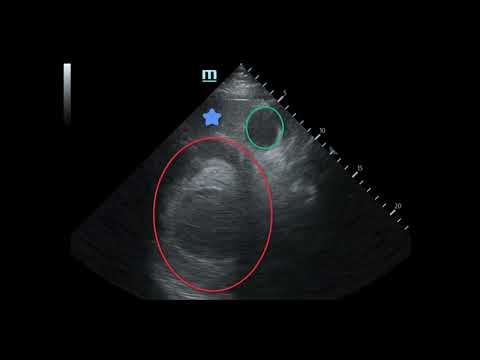

Massive Traumatic Retroperitoneal Hematoma, US 1, Annotated